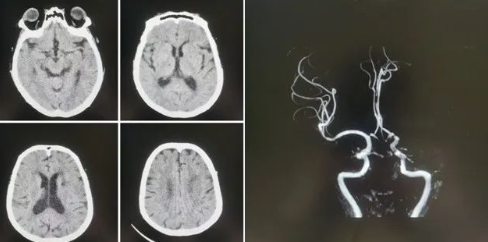

品质国文 | 长春国文医院完成高难度冠脉介入手术 突破复杂病变治疗瓶颈

"所有医院都说没办法,但我们还想再试一次。"回忆起父亲的就医经历,王女士声音哽咽。过去12年里,她的父亲王先生(化名)因冠心病先后植入4枚心脏支架,但胸痛仍反复发作 阅读量:1553